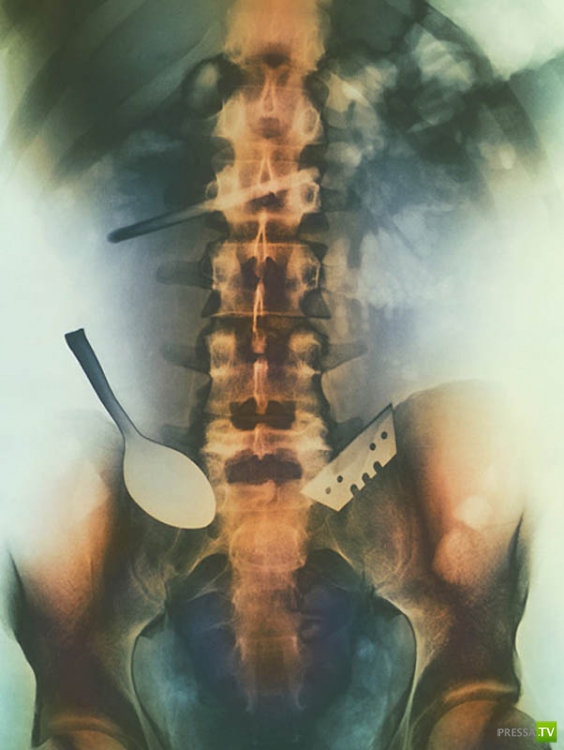

Цветной снимок предметов, которые проглотил пациент, и которые застряли в его кишечнике, включая ложку и лезвие.